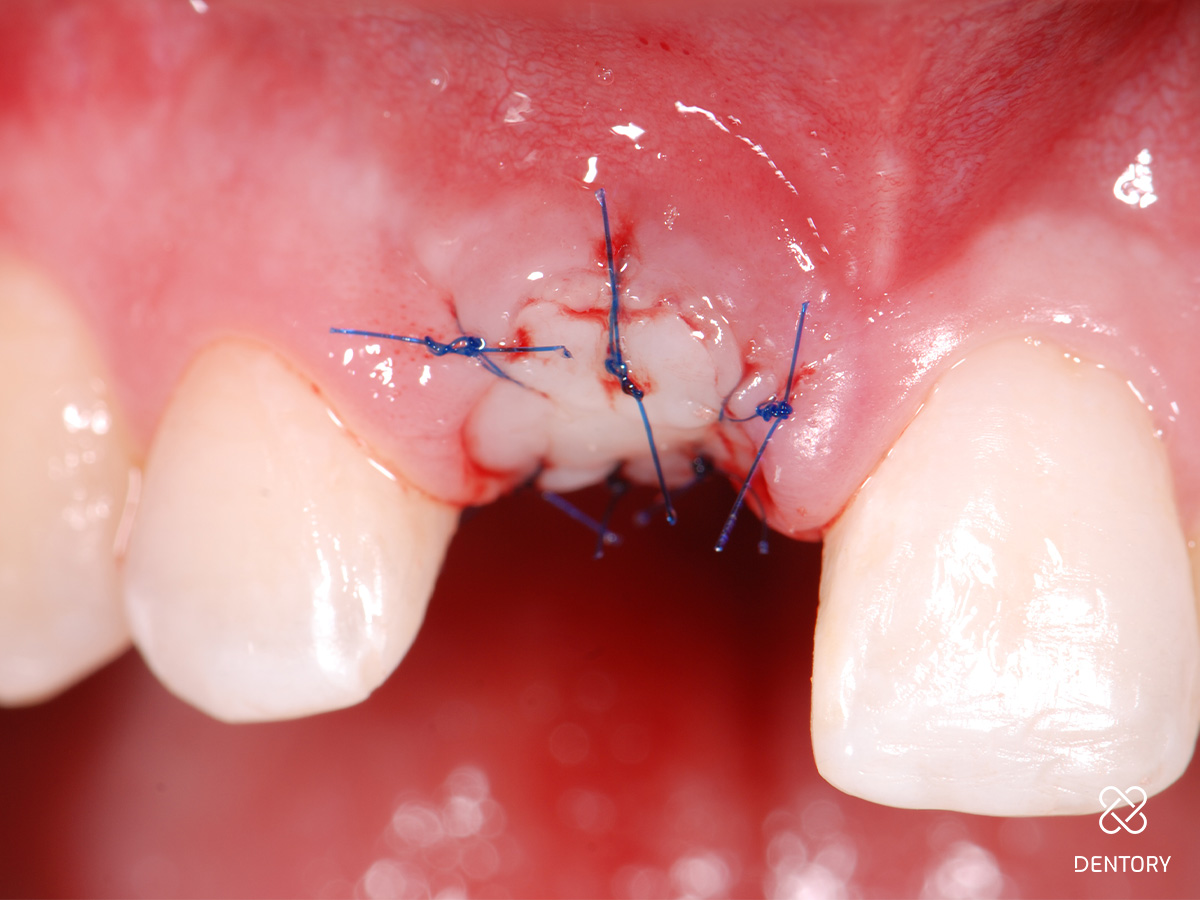

Abbildung 3

...und Entfernung des Zahns durch minimale rotierende Bewegungen mit der Zange.

Abbildung 4

Extrahierter Zahn: Deutliche Resorptionslakune unterhalb der Schmelz-Zement-Grenze bis ins mittlere Wurzeldrittel.